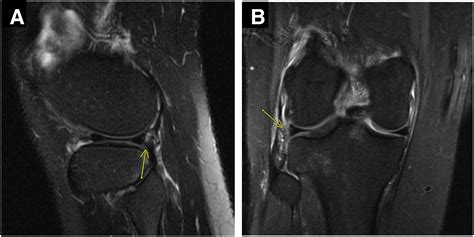

Professional diagnosis often involves a physical exam and imaging tests, such as an MRI, to determine the size and location of the tear. Depending on the results, your doctor may suggest physical therapy to strengthen the muscles surrounding the knee or, in more severe cases, arthroscopic surgery to repair or trim the torn cartilage.